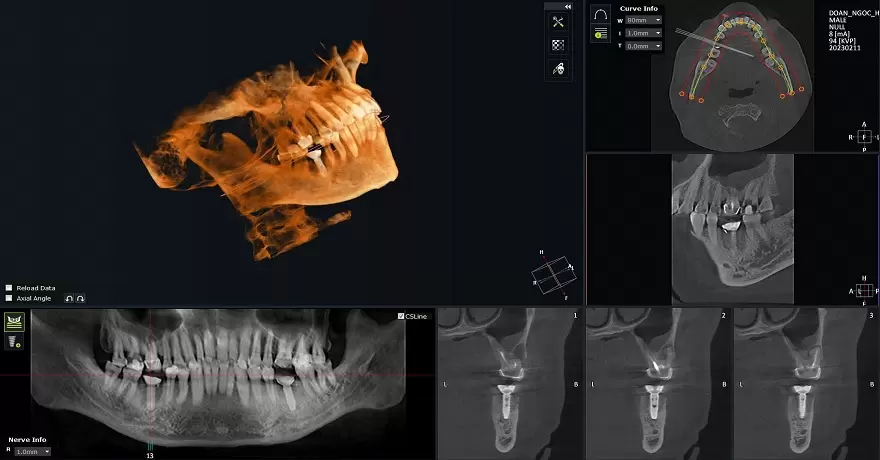

- Tái khám định kỳ sau đó (3, 6, 12 tháng) và chụp X-quang hoặc CBCT để đánh giá mức độ và chất lượng xương mới hình thành.

Nếu bạn đang gặp vấn đề về tiêu xương, túi nha chu sâu hoặc cần tái tạo xương cho kế hoạch cấy ghép Implant, hãy liên hệ ngay với Nha khoa Dr. Green. Chúng tôi sẽ thăm khám, sử dụng công nghệ CBCT để đánh giá chính xác và đưa ra phác đồ phẫu thuật tái tạo xương ổ răng tiên tiến nhất, giúp bạn phục hồi sức khỏe và nụ cười.